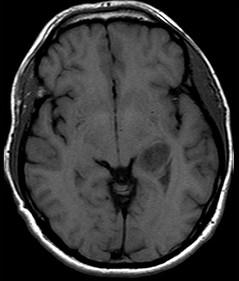

男,53岁,头晕,偏盲,请结合影像图像选择最可能的诊断()A.脑脓肿B.室管膜瘤C.脑膜炎D.脑膜瘤E.多形性恶性胶质瘤

问题 男,53岁,头晕,偏盲,请结合影像图像选择最可能的诊断()

选项 A.脑脓肿 B.室管膜瘤 C.脑膜炎 D.脑膜瘤 E.多形性恶性胶质瘤

答案 E